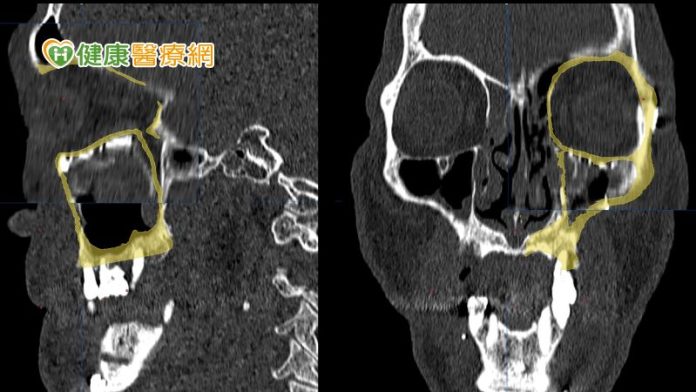

在術前醫師會先透過電腦斷層模擬病人顏面骨骼,並設計出貼近病人原始骨頭構造的立體結構,再利用3D列印技術客製化眼眶骨及顴骨模型,預先調整眼底鈦合金骨板的形狀。黃子桓醫師表示,這不僅能精確地重建,也可以節省手術時間,並提升成功率避免二次手術的可能。

不過,黃子桓醫師提到,如果是已在錯誤位置癒合的顏面骨骨折,重建手術會更為複雜,切斷已癒合的骨塊後,要在立體空間中將骨塊移動到理想位置其實並不容易,在沒有導航的幫助下,手術的不確定性會很高,若術中同步利用導航輔助定位,將能大幅提高精確性。

因此,醫療團隊在術前為李先生模擬、設計精確的復位計畫後,術中也同步利用導航系統協助定位,將錯位的骨塊逐步復位至理想的位置。黃子桓醫師表示,李先生在經過手術後,恢復良好的咬合關係及左右顏面對稱性,住院一週便順利出院。